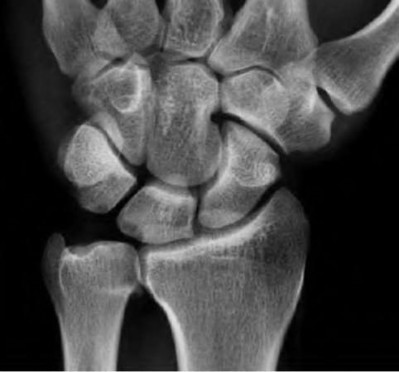

Question 6:

A 22-year-old male falls onto an outstretched hand and sustains a displaced fracture through the proximal pole of the scaphoid. Avascular necrosis of the proximal pole is highly likely due to the disruption of its primary vascular supply. Which vessel provides this critical retrograde perfusion?

Options:

- Superficial palmar branch of the radial artery

- Dorsal carpal branch of the radial artery

- Volar carpal branch of the ulnar artery

- Anterior interosseous artery

- Deep palmar arch

Correct Answer: Dorsal carpal branch of the radial artery

Explanation:

The primary blood supply to the scaphoid is from the dorsal carpal branch of the radial artery, which enters the dorsal ridge of the scaphoid at the waist and courses proximally. This retrograde blood flow makes proximal pole fractures highly susceptible to avascular necrosis and nonunion. The superficial palmar branch provides a minor supply (about 20%) to the distal pole.